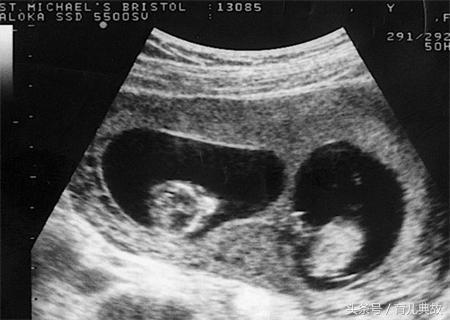

直到怀孕三个月去建卡,第一次产检,有孩子后小姚和老公只祈求宝宝健康就好却没想到宝宝却给了这么大的一个惊喜!医生在做B超的时候说有两个宝宝,胎心胎芽都有。

单胎变双胎的惊喜真的太不可思议了,何其幸运能一次迎来两个宝宝。为了更好的照顾小姚还特意叫小姚婆婆过来,这样老公方能安心的去上班赚钱给孩子买奶粉钱!